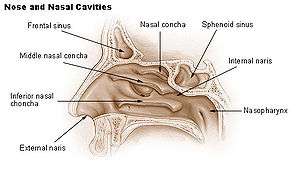

Empty nose syndrome (ENS) is a rare clinical syndrome in which people who have clear nasal passages experience a range of symptoms, most commonly feelings of nasal obstruction, nasal dryness and crusting, and a sensation of being unable to breathe.[1] People who experience ENS have usually undergone a turbinectomy (removal or reduction of turbinates, structures inside the nose) or other surgical procedures that interfere with turbinates; the overall incidence is unknown but it appears to occur in a small percentage of those who undergo nasosinal procedures.[1][2] It appears to be a health care caused condition but its existence as a medical condition, cause, diagnosis and management are controversial.[1] No one disputes that people with the symptoms suffer a great deal.[1][2][3]

There are no objective physical examination findings that definitely diagnose ENS.[1] Generally, one or more turbinates may be reduced or absent when viewed in medical imaging or via endoscope with no sign of physical obstruction, the mucosa will be dry and pale, and there may be signs of secondary infection.[1]

Symptoms of ENS include a sensation of being unable to breathe, a feeling of nasal obstruction and dryness, and crusting, oozing, and foul smells inside the nose from infections.[1] A person with ENS may complain of pain in their nose or face, an inability to sleep and fatigue, and of feeling irritated, depressed, or anxious; they may be constantly distracted by the sense that they are not getting enough air.[1]

The cause may be changes to the mucous membrane of nose and to the nerve endings in the mucosa caused by chronic changes to the temperature and humidity of the air flowing inside the nose, caused in turn by removal or reduction of the turbinates.[1][2] The cause may be direct damage to the nerves caused by surgery, but because as of 2015 there was no technology that allowed mapping of the sensory nerves in the nose it has been difficult to determine if this is a cause.[1] Because the occurrence of ENS is rare and investigators have been unable to identify consistent diagnostic features or precipitating features, psychological causes leading to a psychosomatic condition have been proposed.[1][3][4][6]